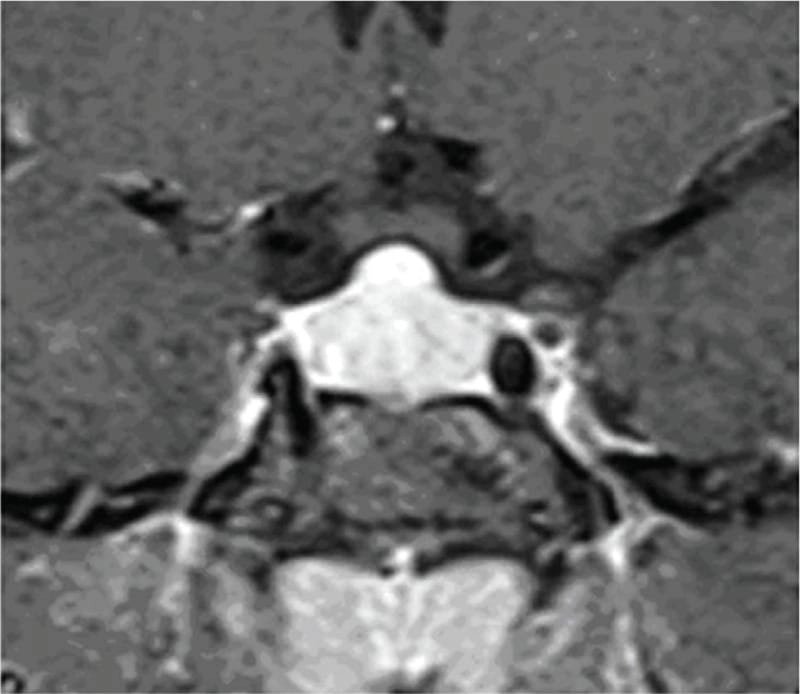

চিকিৎসক তথা আবিষ্কারক সত্যম তিনটি কেসের বিষয় নিয়ে যখন তুলনা করতে নিলেন এবং পুরনো সৃষ্টি ঘাটতে শুরু করলেন তখন তিনি দেখতে পান সবগুলি ক্ষেত্রেই একই রকম সাদৃশ্য অর্থাৎ পিটুইটারি গ্রন্থি মাঝের অংশ এই গ্রন্থি দেখতে খানিকটা প্রজাপতির মতোই এবং তার মাঝের অংশের (প্রজাপতির দেহের উপরের অংশ মাথার মতই দেখতে) উপরের ভাগ সব ক্ষেত্রেই ডোমের মত বা গম্বুজ আকৃতির। তিনি এই ডোম বা গম্বুজ আকৃতি হওয়ার কারণ বিশ্লেষণ করতে গিয়ে দেখেন পিটুইটারির সামনের অংশ যেখানে থাইরোট্রপগুলো থাকে, যেখান থেকে এই টিউমারটি হয়। আর যখনই এটি বাড়বে তখন টমের মতনই তৈরি হবে। অর্থাৎ গম্বুজ আকৃতির। আর সেখান থেকেই ডোম-সাইনের উৎস অর্থাৎ আবিষ্কার।

MRI-তে এই হাইপারপ্লাসিয়া সাধারণত গম্বুজ-আকৃতির ও সমমিত হয় এবং হোমোজেনাস সিগনাল ইন্টেনসিটি দেখায়, যেখানে সাধারণ নন-ফাংশনাল পিটুইটারি অ্যাডেনোমা নানা আকার ও অসমতা নিয়ে দেখা যায়।

তাঁর দাবি, MRI-তে ‘DOME Sign’ থাকা এবং TSH বাড়তি থাকলে, সেটি হাইপোথাইরয়েডিজম-জনিত হাইপারপ্লাসিয়ার সম্ভাবনার কথা নির্দেশ করে এবং এই রোগীদের শুধুমাত্র লেভোথাইরক্সিন দিয়ে চিকিৎসা করলে পূর্ণ আরোগ্য সম্ভব।